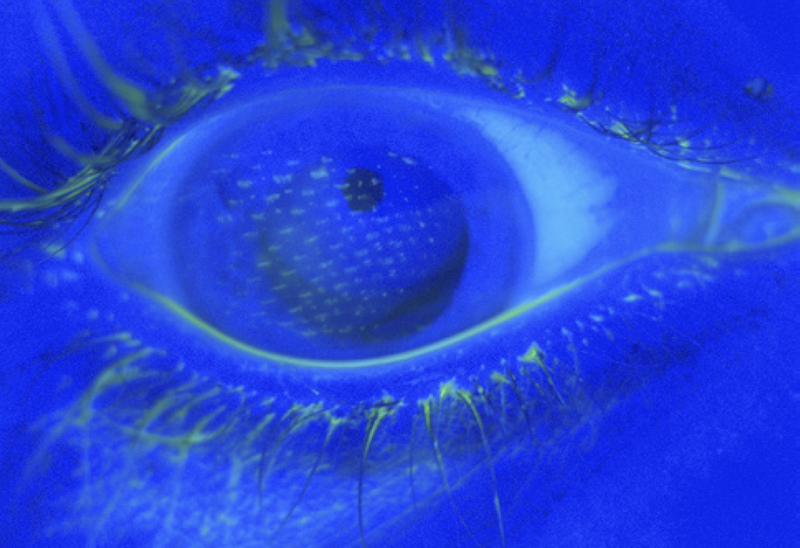

File:Airbag-corneal-abrasion2.png

University of Michigan Kellogg Eye Center |

Ryan James Fante, M.D. Jonathan D. Trobe, M.D. |